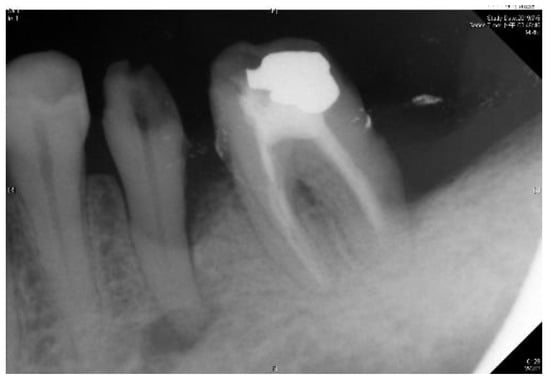

The radiographic finding of a potential endodontic pathosis is an essential part of endodontic assessment in daily dental practice. Apical periodontitis (AP) is an inflammatory response in the apical periodontium that often results from tooth root canal microorganisms, which may cause apical bone resorption, resulting in apical lesion [1]. Thus, diagnosis of periapical pathology has always been a topic of concern in endodontics. Identifying the periapical pathology of nonvital teeth is a key factor of successful treatment planning and prognosis evaluation [2]. Due to the fact that tooth with periapical pathosis is sometimes asymptomatic, it is often only detected via routine radiographic examination [3]. Few diagnostic tests provide as much useful information as dental radiography. In general, apical endodontic pathosis appears radiographically as bone loss in the area of the periapex and presenting radiolucent area at the apex of the root. Among all types of dental radiography, the periapical film which like Figure 1 is most commonly used in apical lesion diagnosis clinically [4].

Figure 1. Periapical film database.